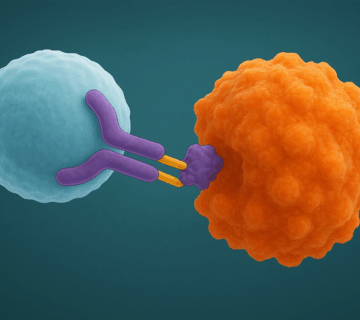

إيمريليس ليس علاجًا تقليديًا كالعلاجات الكيميائية المعتادة، بل هو نوع جديد يُعرف بـ”العلاج الموجّه” أو “مركّب الجسم المضاد والدواء” (ADC). يُمكن تخيّله كـ”قنّاصة طبية”، حيث يتعرف على الخلايا التي تحتوي على نسبة عالية من بروتين c-Met، ويقوم بإيصال الدواء مباشرة إليها، مما يقلل من الضرر على الخلايا السليمة المحيطة.

يتكوّن الدواء من جسم مضاد يلتصق بالخلايا المصابة، ويرتبط به دواء قوي جدًا مخصص لقتل تلك الخلايا. وبهذا الأسلوب الدقيق، يستطيع إيمريليس أن يستهدف المرض بدقة دون التسبب بنفس مستوى الآثار الجانبية القوية التي تُعرف بها العلاجات التقليدية.